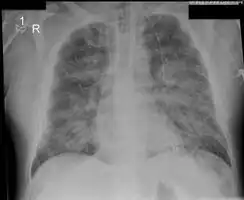

Acute pulmonary edema

Low oxygen saturation and disturbed arterial blood gas readings support the proposed diagnosis by suggesting a pulmonary shunt. A chest X-ray will show fluid in the alveolar walls, Kerley B lines, increased vascular shadowing in a classical batwing peri-hilum pattern, upper lobe diversion (increased blood flow to the superior parts of the lung), and possibly pleural effusions. In contrast, patchy alveolar infiltrates are more typically associated with noncardiogenic edema[8]